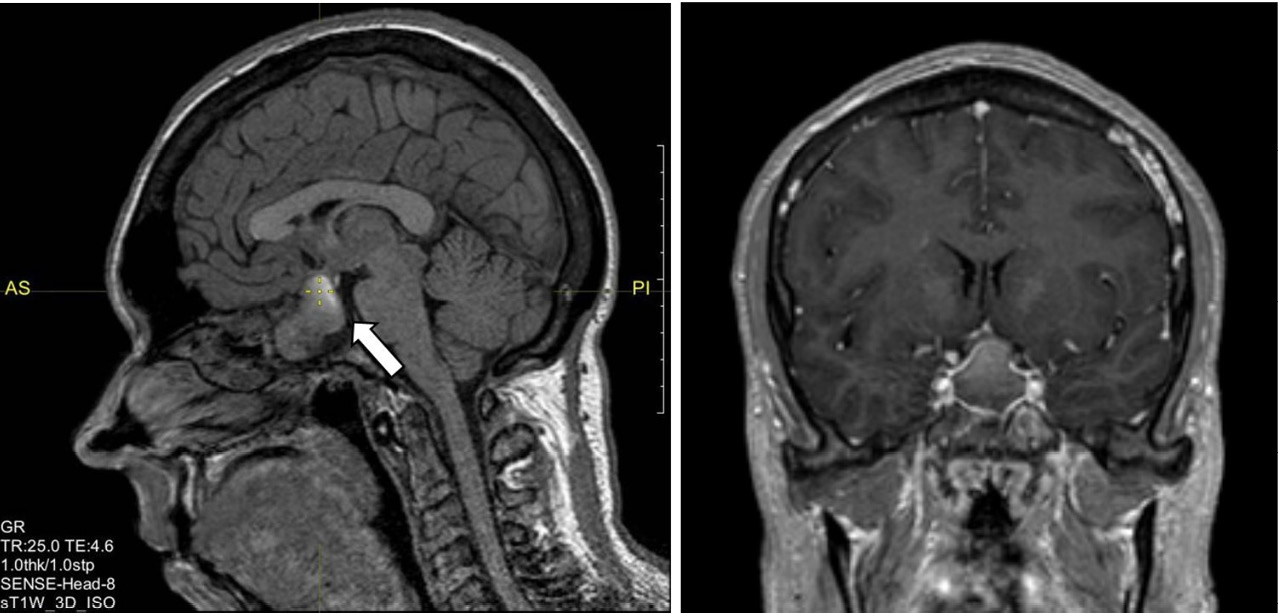

С 11 по 17 января 2023 г. – госпитализация в эндокринологическое отделение БУЗ УР «1 РКБ МЗ УР». При осмотре пациентка предъявляет жалобы на набор веса на 13 кг за последние 2 года, избыточную потливость, храп, боли в суставах пальцев рук, коленных суставах, повышение артериального давления до 145/100 мм рт. ст., сопровождающееся головными болями. На постоянной основе пациентка принимает левотироксин натрия 150 мкг/сут; гидрокортизон 20 мг/сут вместо рекомендованных ранее 15 мг/сут (забыла снизить дозу препарата), эстрадиол + дидрогестерон 1/10 мг (1 таблетка вечером внутрь). По данным УЗИ щитовидной железы от 13.01.2023 (в проекции долей и перешейка ткань щитовидной железы не визуализируется, ложе без особенностей, шейные лимфоузлы не увеличены), лабораторных обследований (ТТГ – 0,13 мкМЕ/мл (0,4–4,0), тиреоглобулин менее 0,20 нг/мл, антитела к тиреоглобулину менее 20,0 МЕ/мл от 12.01.2023) зарегистрирована биохимическая ремиссия папиллярного рака щитовидной железы. На МРТ от 12.01.2023 визуализировано вторичное «пустое» турецкое седло как исход апоплексии гипофиза, данных за рецидив аденомы не получено (рис. 3).

Рис. 3. Магнитно-резонансная томография гипофиза с контрастным усилением. «Пустое» турецкое седло (указано стрелкой)

По данным лабораторного обследования от января 2023 г. ИФР-1 – 171,3 нг/мл (83–220), базальный уровень СТГ – 1,56 нг/мл, что позволило констатировать ремиссию акромегалии. Пациентка осмотрена офтальмологом – заподозрена частичная атрофия зрительного нерва, рекомендована его оптическая когерентная томография. По результатам биохимического анализа крови повторно была выявлена дислипидемия (от 12.01.2023 липопротеиды низкой плотности – 3,62 ммоль/л), назначена терапия статинами. По данным эхокардиографии от 13.01.2023: систолическая функция левого желудочка удовлетворительная, диастолическая дисфункция левого желудочка по I типу, размеры камер сердца в норме, недостаточность митрального клапана I степени, недостаточность трикуспидального клапана I степени.